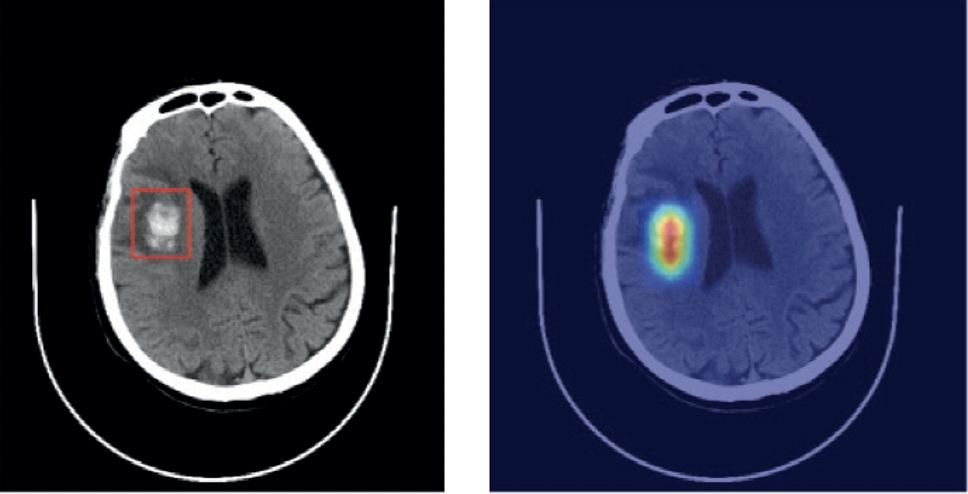

Self-taught AI detects disorders from head scans

This intuitive AI can sort through scans to diagnose stroke, brain haemorrhage, brain tumors and skull fractures.